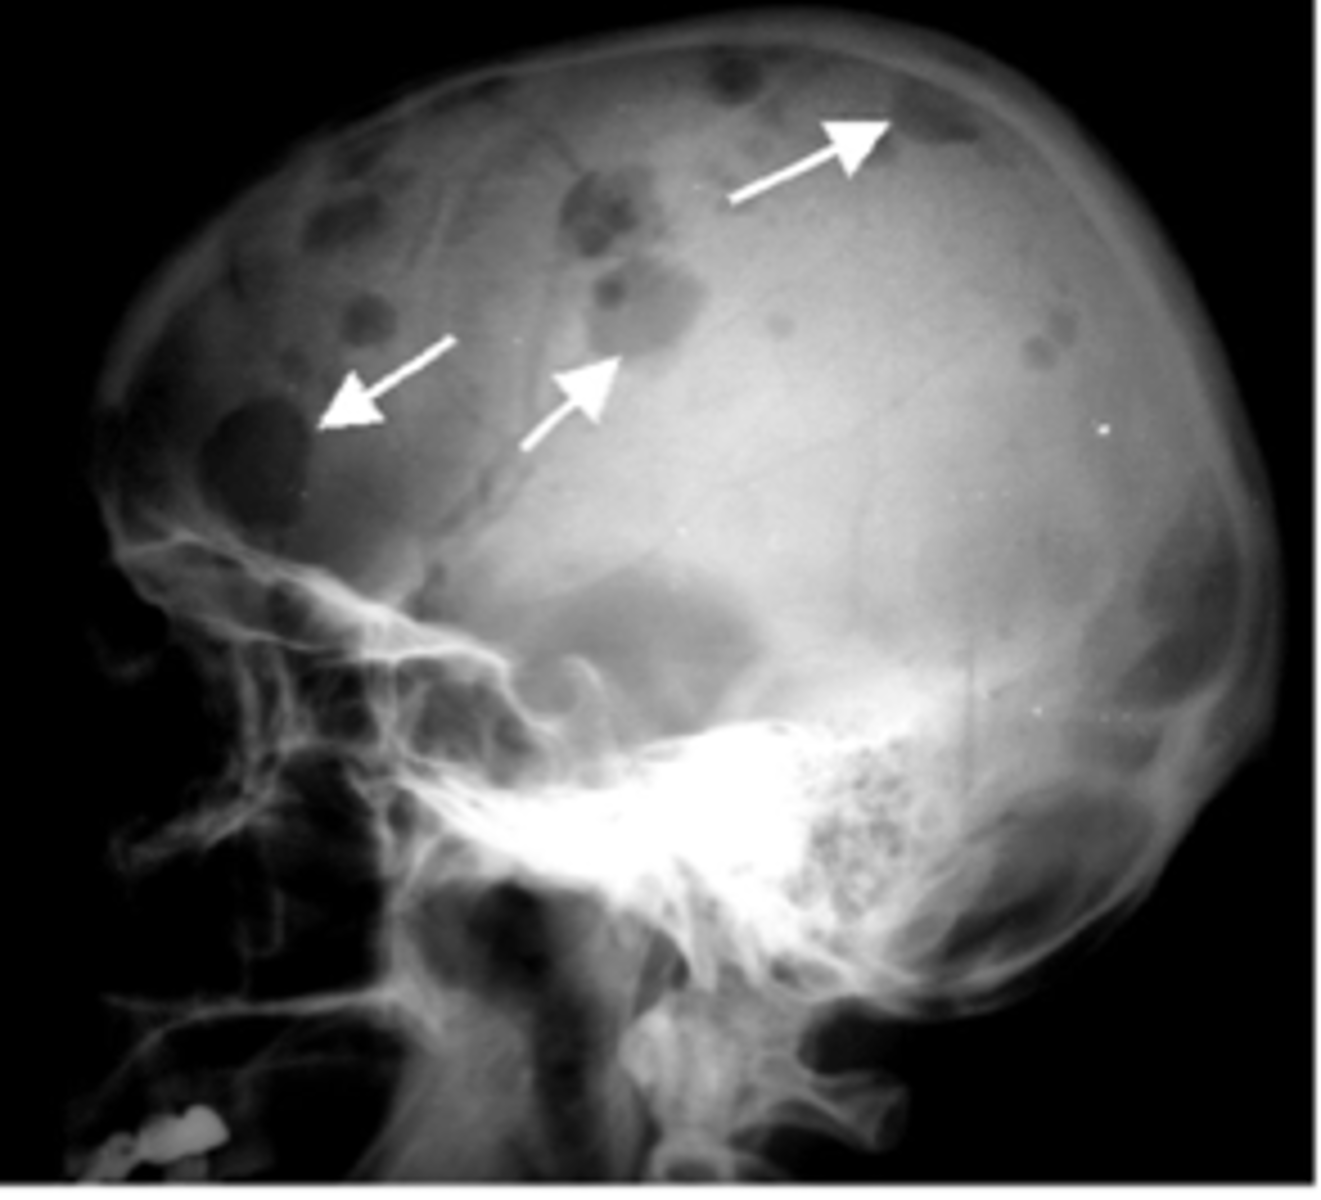

Defining characteristics of Multiple Myeloma

<p>High antibody level, osteolytic lesions in bones</p>